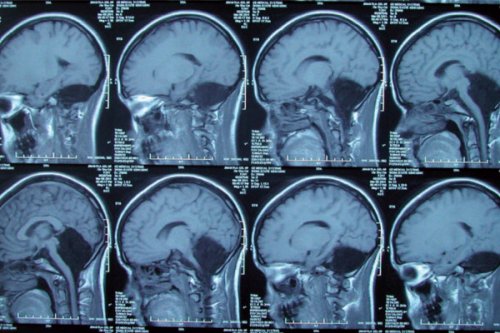

山东一名24岁女子因为严重晕眩、恶心,到医院求诊,没想到经过检查,医生竟然发现该名女子天生就有“脑洞”,没有小脑!

根据《New Scientist》报导,女子就医后,向医生说明走路时常不稳跌倒,母亲也表示她小时候到6岁时都不太会说话,到7岁才会走路。医生安排电脑断层扫描,报告出来后,发现原本应该是小脑的地方竟然是空的,让医生大吃一惊。

小脑的位置在头骨后方,主要作用是控制运动和平衡,也被认为与说话能力有关,所占脑部的总体积仅10%左右,却含有50%的神经元。小脑出问题可能导致严重的精神障碍、运动障碍、癫痫,或造成脑脊液积聚在这一空洞的区域。然而,这名女子天生有脑洞,却仅有轻度的语言问题,发音稍微含糊。

这名女子的初步检查结果,发表在最新一期的《脑科》(the journal Brain)。通常,世界上这类病患很早就会死亡,在尸检才发现问题,但她却活到24岁了,生活大部分的时间都很好。医界好奇,难道是她的大脑皮质取代了小脑的功能?